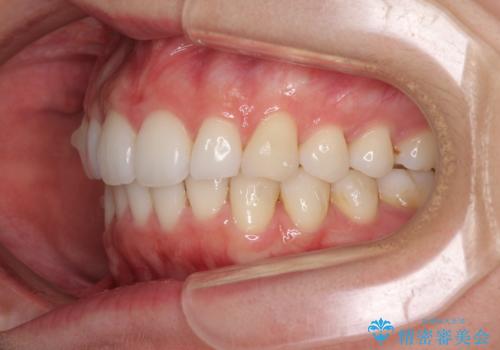

- 上下前歯の叢生を気にして来院された患者様です。

以前矯正をした後戻りということで、歯列不正はそれほど大きくなかったため、インビザライン・ライトを用いて矯正治療を行うこととしました。

前歯のデコボコが残っており、シミュレーション通りに動いていない部分がありましたが、再矯正であることやご本人の満足いくところまでデコボコが改善されたとのことで、治療を終了することとしました。